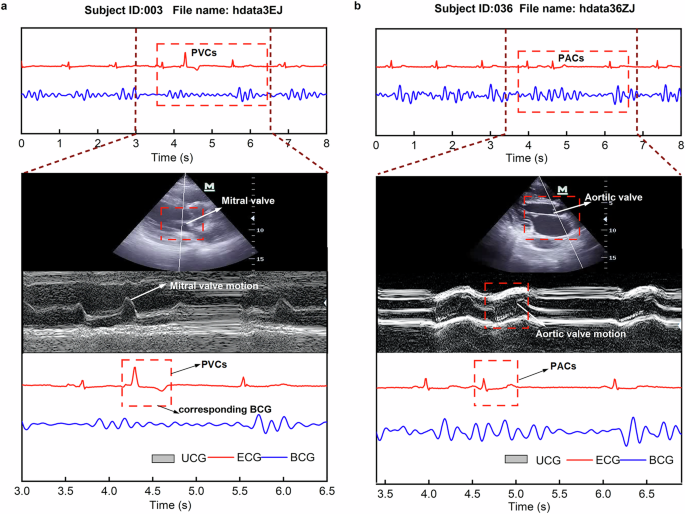

A qualitative analysis was conducted on two participants(003 and 036) with cardiac arrhythmias to investigate the relationship between BCG signals, ECG, and M-mode ultrasound data (Fig. 6). In the case of the first patient with PVCs (Fig. 6a), an abnormality was observed in the ECG signal, but no corresponding mechanical response was detected in the BCG signal. Ultrasound imaging revealed that the mitral valve did not show significant movement during the PVCs event, indicating a lack of mechanical response to the abnormal electrical signal.

BCG and ECG signals with synchronized M-mode echocardiography in arrhythmic patients. (a) Mitral valve imaging (Subject ID: 003, hdata3EJ). BCG and ECG signals are shown in the upper panel, with a magnified segment highlighting an arrhythmic event. The lower panel presents the corresponding M-mode echocardiography of the mitral valve. (b) Aortic valve imaging (Subject ID: 036, hdata36ZJ). Similar to a, the upper panel displays BCG and ECG signals, while the lower panel shows the M-mode echocardiography of the aortic valve, synchronized with the arrhythmic episode.

In contrast, for the second participant with premature atrial contractions (PACs, Fig. 6b), the BCG signal remained present and showed a slightly earlier peak than expected, consistent with the prolonged RR interval in ECG. The M-mode trace of the aortic valve captured this timing variation as well. These observations suggest that certain arrhythmic events manifest as visible changes across multiple modalities, including ECG, BCG, and ultrasound, demonstrating both temporal and morphological consistency.